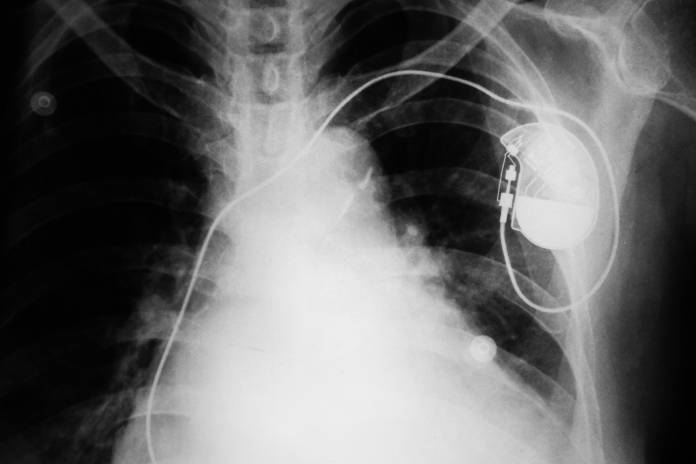

Herzschrittmacher op wie lange krank. Wie lange bin ich krankgeschrieben. Nach der etwa einstündigen Operation werden Sie für weitere 24 Stunden überwacht um frühzeitig Blutungen oder ein Verrutschen der Sonden zu erkennen. Zuvor findet noch eine Kontrolle und gegebenenfalls Nachjustierung des Gerätes statt.

Ich habe vor fast zwei Monaten einen Herzschrittmacher implantiert bekommen. Bei modernen Herzschrittmachern beträgt die Lebensdauer der Batterie zwischen fünf und zehn Jahren. Für den Schrittmachereinbau sind Sie wenn der Eingriff geplant ist in der Regel zwei bis drei Tage im Krankenhaus.